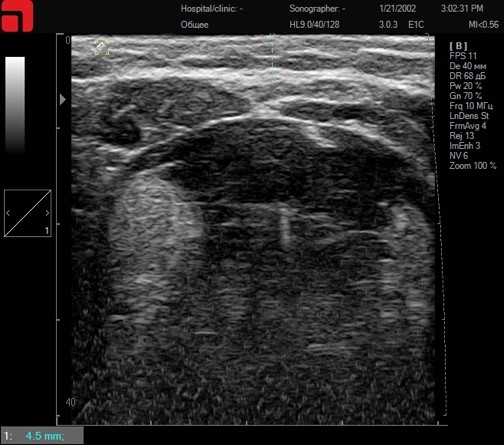

Соединительная ткань при сильном надавливании

Рис. 2. Соединительная ткань при сильном надавливании.

Как видно на данном слайде, интенсивное надавливание на манипулу распластывает ПЖК, приближая СМАС-слой к поверхности кожи, делая его более доступным для лифтинговых насадок (3 мм M7 и 4,5 мм D4). Но из-за высокой плотности дермы и выраженной ПЖК, у данного пациента этого будет недостаточно. Это редкие ситуации в клинической практике, но они возможны. В таком случае дополнительно приподнять СМАС-слой, распластав мягкие ткани, можно изнутри, установив интраоральную каппу или заложив ватные диски между зубами и слизистой оболочкой щек.